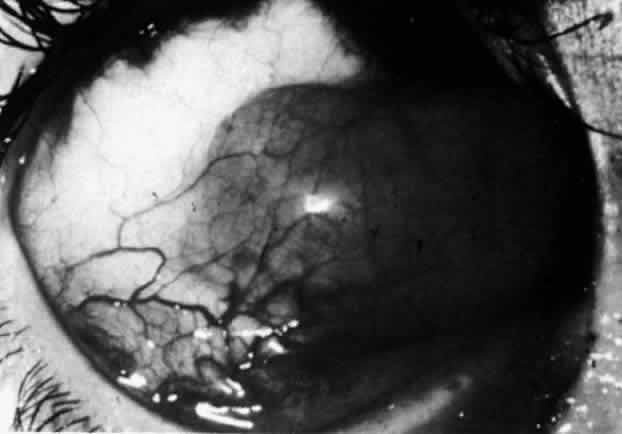

The redness of simple episcleritis may be intense, varying from a fiery-red or a brick-red discoloration to a mild red flush, but it does not have the bluish tinge that is seen in scleritis. The distribution is usually sectorial but can involve the whole anterior segment of the globe. The episcleral vessels are engorged but retain their normal radial position and architecture (Figs. 13 and 14; Color Plate 1A). In simple episcleritis, there is a diffuse edema of the episcleral tissues. These tissues are sometimes infiltrated with gray deposits that appear yellow in red-free light. Surprisingly, the eye is rarely tender to the touch.

Fig. 13. Infiltration of the episclera in which the superficial episcleral vessels show maximal congestion. Conjunctival vessels are slightly congested, as is the deep episcleral plexus, whose irregular criss-cross pattern can be seen deep to the radially arranged superficial episcleral plexus.

Fig. 14. Diffuse inflammation. Superficial vessels are maximally engorged and retain their radial pattern and architecture. (See Figures 27 and 34.) (Watson PG: Connective tissue disorders and the eye. In: Recent Advances in Ophthalmology, Vol 5, pp 214–277. London, Churchill-Livingstone, 1975)